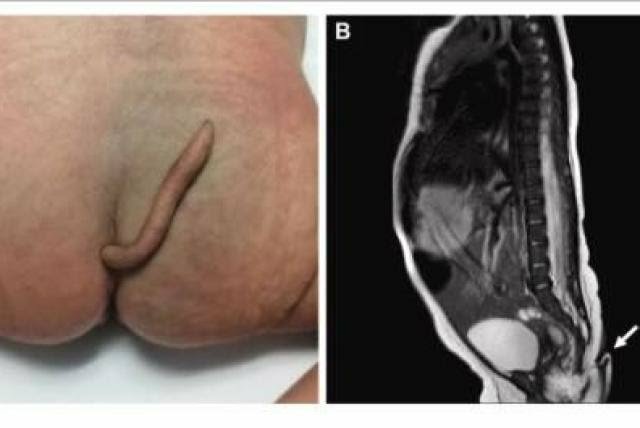

Un bebé del sexo femenino nació con una cola de alrededor de seis centímetros de largo en el estado de Nuevo León, México, así lo confirmó el Journal of Pediatric Surgery Case Reports, medio que le dio seguimiento al caso poco común en el país azteca.

De acuerdo con el reporte dos médicos, dirigidos por el doctor Josué Rueda, el embarazo no tuvo complicaciones, pero cuando revisaron al recién nacido vieron que la extremidad sobresalía al final de su coxis. Al parecer, podía moverse sin causarle dolor a la bebé, pero no tenía ninguna clase de movimiento espontáneo. Durante las pruebas, la niña lloró al ser pinchada con una aguja, lo que probaba que había conexiones nerviosas.

A los dos meses del parto, la pequeña regresó a ser examinada por los especialistas. Según describieron en el reporte para la revista científica, tenía «el peso y el crecimiento adecuado para su edad». La cola, así mismo, había crecido 0,8 centímetros «sin evidencia de lesiones cutáneas».

Luego de la valoración, determinarón que debía extirparse, por lo que anestesiaron a la bebé y le retiraron la cola en un proceso que no tuvo complicaciones.